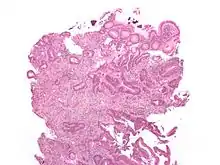

КРР — аденокарцинома, тобто епітеліальна пухлина, що походить з залозистого епітелію, що формує мукозний шар стінки товстої кишки. КРР демострує інвазію в стінку кишки, підслизовий шар та м'язовий шар. Клітини КРР мають неправильні тубулярні структури та бідну строму.